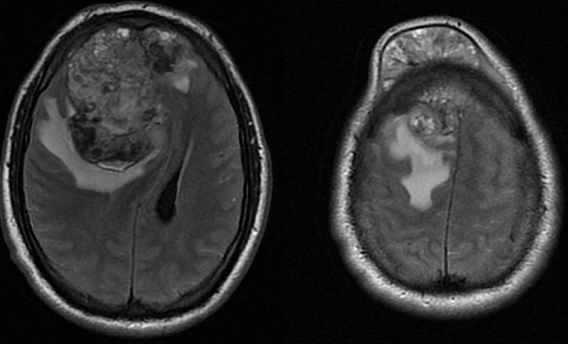

A 24-year-old man presented with a 9-month history of a progressively increased painless left testicle. One month before admission, a round tumor appeared on his right forehead; this was associated with a persistent frontal headache of moderate intensity. The tumor progressively increased and was accompanied by altered consciousness characterized by stupor and confusion, which motivated his being taken to the emergency room. On initial evaluation, he had a Glasgow Coma Score of 13 with a proportionate left hemiparesis and a left pyramidal syndrome. The left testicle was increased in size, indurated, painless to palpation, and associated with a large left hydrocele. A brain MRI was performed that showed a heterogeneous lobulated intra and extracranial right frontal lesion. The intracranial component was vascularized and hemorrhagic, 8.2 x 7.1 x 6.8 cm with partially defined borders and vasogenic edema which shifted the midline 30 mm to the left and infiltrated the superior sagittal sinus. This predisposed right subfalcine and uncal herniation as well as left hydrocephalus. Extension studies showed metastatic lung and liver lesions. Laboratory studies revealed an alpha-fetoprotein level of 1210 ng/mL with a normal β-hCG level (1.11 mIU/mL). A diagnosis of poor-risk germ-cell tumor was made and a chemotherapy scheme was planned; however, the patient died due to acute neurological deterioration 48 hours after admission.